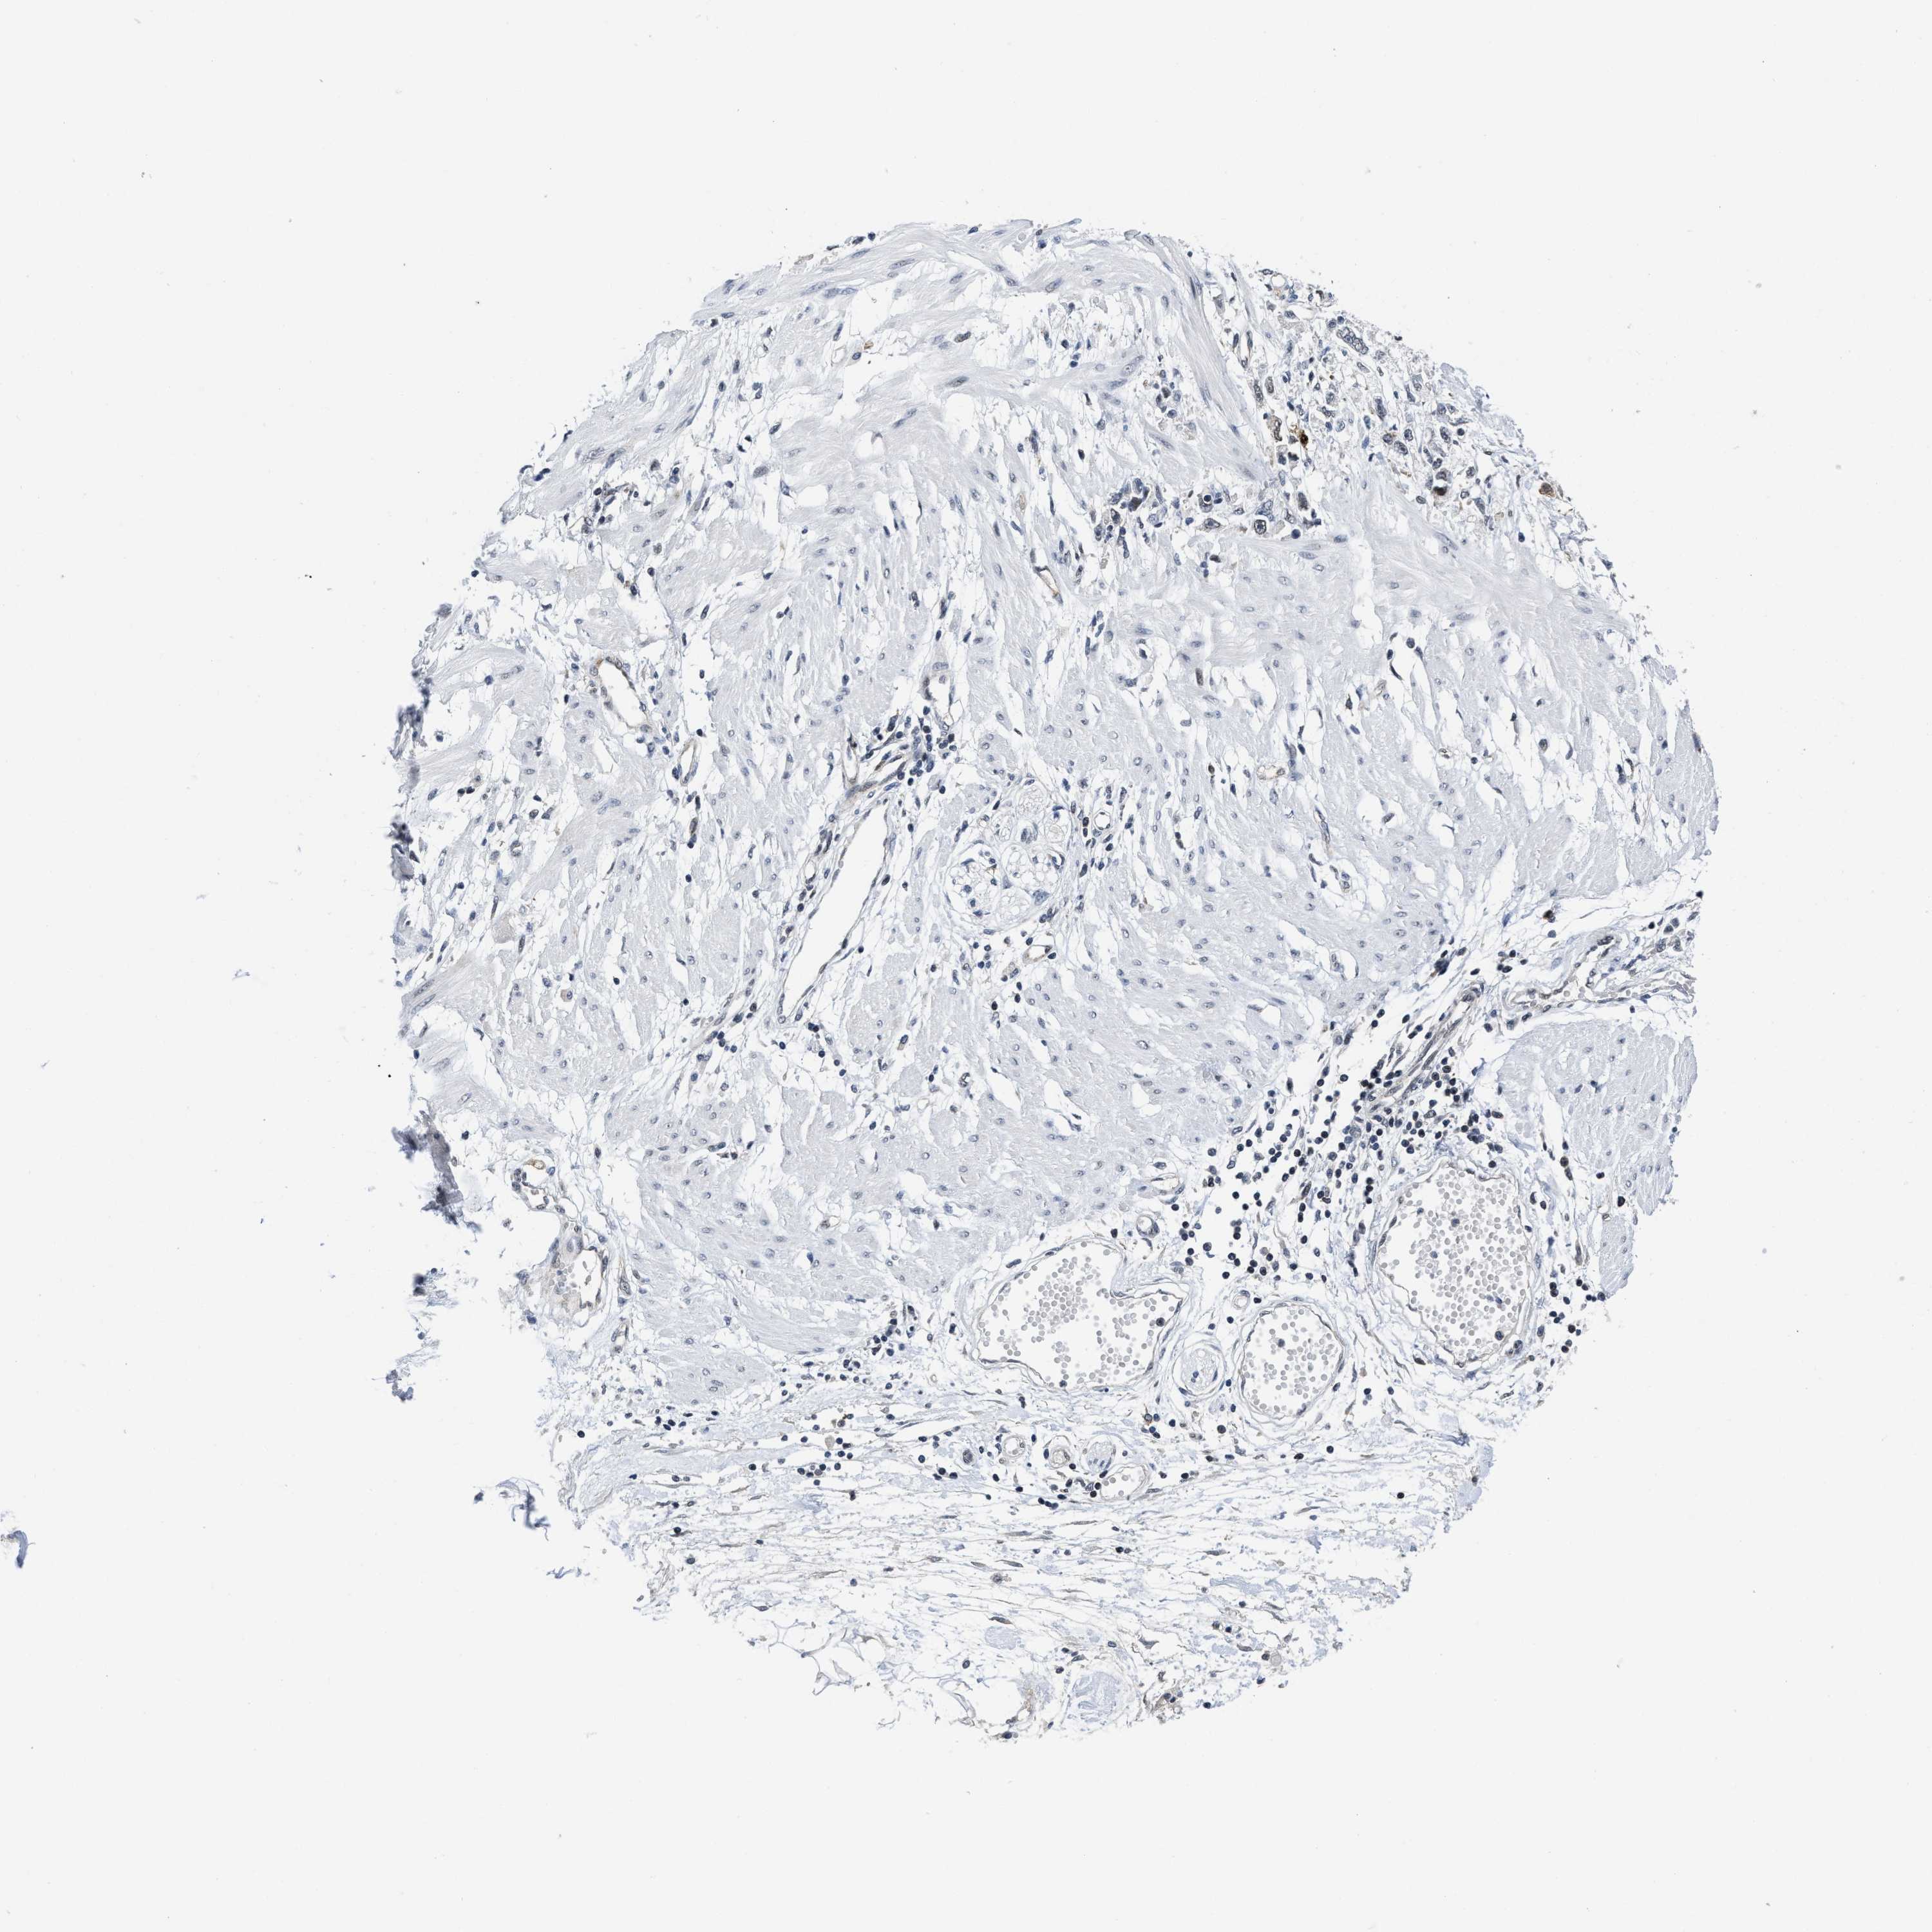

STOMACH CANCER - Protein expressioni

A mouse-over function shows sample information and annotation data. Click on an image to view it in a full screen mode. Samples can be filtered based on level of antibody staining by selecting one or several of the following categories: high, medium, low and not detected. The assay and annotation is described here.

Note that samples used for immunohistochemistry by the Human Protein Atlas do not correspond to samples in the TCGA dataset.

Antibody stainingi

Antibody staining in the annotated cell types in the current human tissue is reported as not detected, low, medium, or high, based on conventional immunohistochemistry profiling in selected tissues. This score is based on the combination of the staining intensity and fraction of stained cells.

Each image is clickable and will lead to virtual microscopy that enables deeper exploration of all samples and also displays staining intensity scores, fraction scores and subcellular localization as well as patient and tissue information for each sample.

Antibody HPA001275

Antibody CAB017442

Staining

High

Medium

Low

Not detected

Intensity

Strong

Moderate

Weak

Negative

Quantity

>75%

75%-25%

<25%

None

Location

Nuclear

Cytoplasmic/membranous

Cytoplasmic/membranous,nuclear

Adenocarcinoma, NOS

Adenocarcinoma, High grade